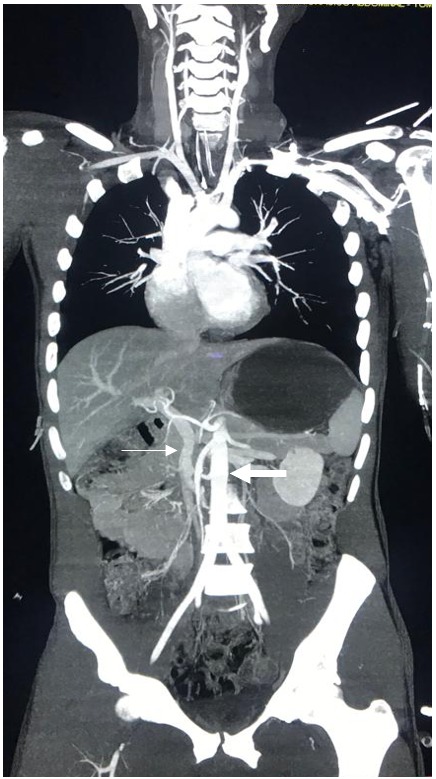

Implementación de protocolos de tomografía corporal total

Mundialmente, existen múltiples protocolos de tomografía corporal total sin consenso sobre cuál de ellos es el ideal 10,17-20. La mayoría de los protocolos incluyen imágenes de cerebro y columna cervical sin contraste seguidas por dos pasadas en tórax, abdomen y pelvis con contraste, la duración de la adquisición del estudio varía entre 2 a 5 minutos. Como se mencionó anteriormente, la evaluación radiológica de los pacientes politraumatizados debe ser rápida, sin interrumpir la resucitación y con la mínima exposición a radiación ionizante. Además, en la imagen se deben obtener tanto la fase arterial como la venosa para lograr una adecuada evaluación de todas las posibles lesiones orgánicas y/o vasculares 21,22. Con este fin, en nuestra institución en Cali, Colombia hemos implementado el uso de la tomografía corporal total en todos los pacientes politraumatizados con o sin signos de inestabilidad hemodinámica; se estableció un protocolo de tomografía corporal total de una sola pasada, con el cual en sólo 175 segundos se obtiene una tomografía simple de cráneo y uno contrastado desde el cuello hasta la sínfisis púbica (Tabla 1), el resultado es una sola imagen de alta resolución donde se visualizan de forma simultánea las fases arterial y venosa (Figura 1).

Figura 1 Fase arterial y venosa en el TAC-Corporal Total (la flecha gruesa muestra la fase arterial y la flecha delgada muestra la fase venosa)